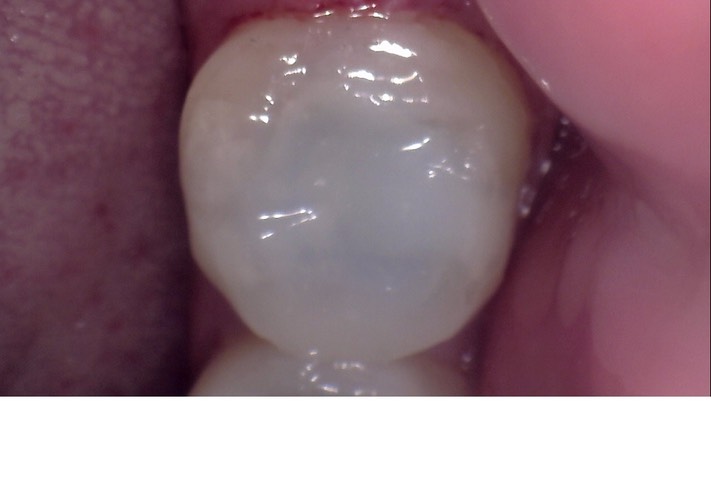

Kris Nip #18 pre-op